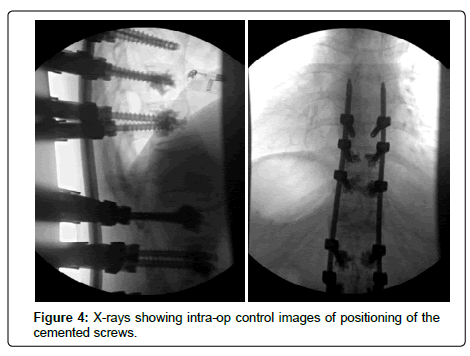

This patient was submitted in February 2016 to the percutaneous transpedicular fixation of D10-D11-D12-L2-L3-L4, with cemented screws. She refused surgery by anterior approach with L1 corpectomy and “cage” placement.

The postoperative period was uneventful, having started deambulation with Jewett’s orthosis. Five months after surgery, there was a clear improvement in painful complaints and no need to wear the vest. Signs of neurological damage were never objectified. Postoperative radiographs demonstrate a frank improvement of the kyphotic angle (37) and the vertical sagittal axis (12.9 centimeters). The control CT scan performed in November 2016 revealed fracture with signs of progression for consolidation (Figure 1-7).